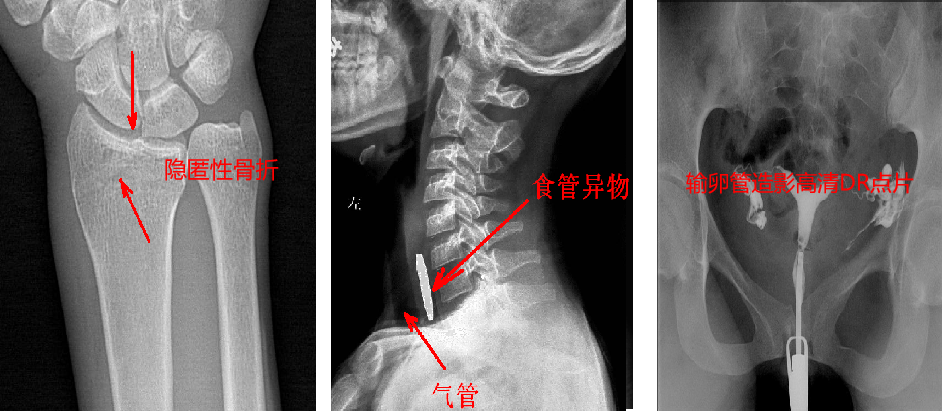

靜態(tài)DR最大的缺陷來自于盲拍,因此造成誤診發(fā)生率高,是保證診斷準確性的巨大阻礙因素。在靜態(tài)拍片中,部分特殊病灶容易被遮掩而導致漏診,在一些特殊造影上需要憑借醫(yī)生的臨床經(jīng)驗才能獲取有效影像。而動態(tài)DR依靠可視化高速高清點片功能,改變了傳統(tǒng)的盲拍模式。動態(tài)DR在低劑量數(shù)字透視的情況下,能夠進行疑似病灶部位點片,極速精準獲取有效信息,同時可即時回放視頻信息,在臨床上極大地提高了病變的檢出率,降低漏診誤診。

與此同時,動態(tài)DR的成像視野與精度也勝于靜態(tài)DR。動態(tài) DR17×17 英寸方形幅面進行動態(tài)成像,能夠?qū)鹘y(tǒng)動態(tài)造影幅面小的問題全部解決,同時由于幅面較大,臨床操作技師能夠在一個大的幅面下觀察診斷,當看到病變部位時實時高清點片,從而很好地捕捉到病變點,也大大降低了檢查時間。